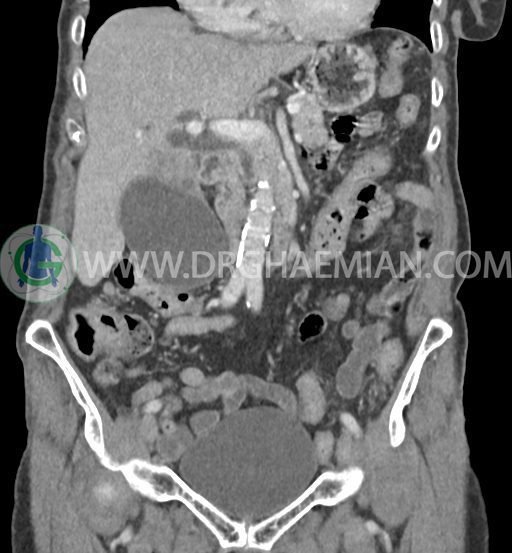

در سی تی اسکن اسپیرال شکم و لگن با و بدون کنتراست خوراکی و وریدی (مولتی دیدکتور 16 با مقاطع ظریف و بازسازی های ساژیتال و کرونال) :

تصویر توده اندکی هیپودنس (HU=40 ) به ابعاد 30x40mm در سگمان 4b کبد ، با حدود ناواضح با enhancement هتروژن و قابل توجه پس از تزریق کنتراست ( HU=70 )، با شواهد تهاجم به گردن کیسه صفرا

تصویر شبیه به توده به قطر 15mm بین خم کبدی کولون و سگمان 6 کبد و قطب تحتانی کلیه راست و به قطر 8mm در انتریور سکوم مطرح کننده توده های peritoneal

کیسه صفرای دیلاته حاوی اسلاژ و سنگ های فراوان به قطر 5mm تا 10mm مطرح کننده کولانژیوکارسینوما

دیلاتاسیون خفیف مجاری صفراوی داخل کبدی

accessory spleen به قطر 12mm مجاور قسمت تحتانی هیلوم طحال